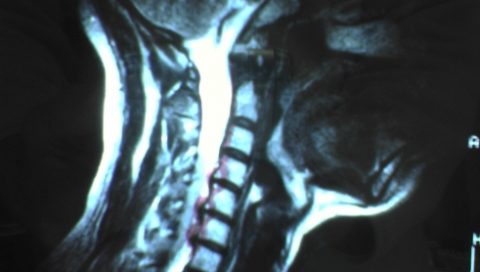

【映像を使うと何が変わる?】ヘルニア手術での映像活用方法

映像を医療に活用することは、最近では全く珍しいことではなくなりました。たとえば、ヘルニアの手術などでも、映像は活用されているのです。ヘルニア手術ではどんな風に映像が活用されているのか、御存じでしょうか? ヘルニア手術の方 […]